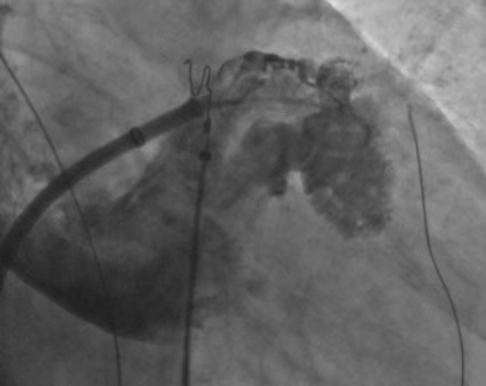

脉冲消融完成后进行经皮左心耳封堵术,交换鞘管,送入左心耳封堵器介入输送装置并沿尾端送入猪尾导管进行左心耳造影,测量后决定选LAAO-I28/38mm封堵器并封堵,造影及心腔内超声证实封堵器位置良好,符合“PAST”原则,成功。